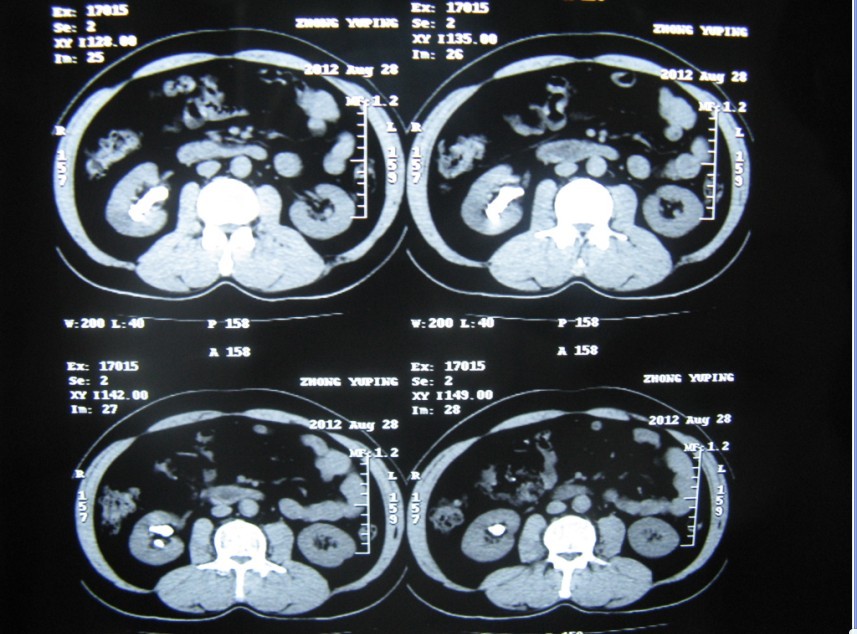

3 术前CT片可以看到结石位于右肾盂及中下各盏,无肾积水

微信服务号